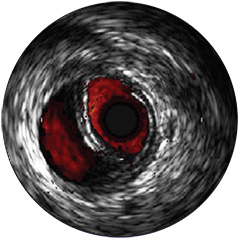

Einführung der völlig neue Anwendungsplattform IntraSight von Philips – Zusammenspiel von Bildverarbeitung, Physiologie, Koregistrierung und Software für eine optimale Patientenversorgung. IntraSight bietet eine umfassende Palette klinisch bewährter Modalitäten wie iFR/FFR, IVUS und Koregistrierung* für einfachere komplexe Interventionen, schnellere Routineverfahren und eine verbesserte Patientenversorgung.

IntraSight ist auf Basis einer intelligenten, anwendungsbasierten Plattform konzipiert, die sich bei neuen verfügbaren Anwendungen und Modalitäten an die sich ändernden Anforderungen Ihres Labors anpassen lässt – und das ohne neue Hardware erwerben zu müssen. Nur IntraSight von Philips bietet Ihnen erstklassige Bildverarbeitungs- und Physiologie-Tools mit iFR, iFR-Koregistrierung*, FFR, IVUS, IVUS-Koregistrierung* und Angio+*. Dank seiner modularen Architektur bleibt IntraSight über die neuesten Entwicklungen und wichtigen Sicherheitsupdates auf dem Laufenden.

Digitale IVUS- Bildverarbeitung

Abbildung 3